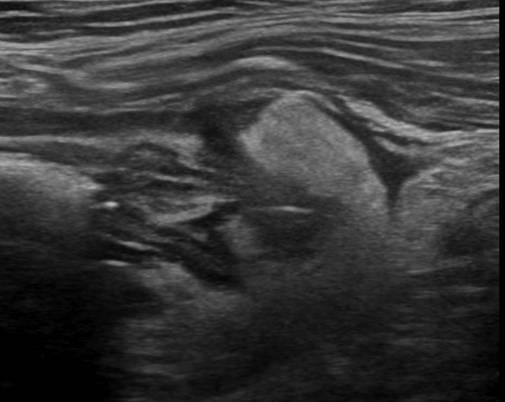

Viêm túi thừa - Ảnh 4

Viêm túi thừa

» Thông tin: Nam giới – 66 tuổi.

» Lâm sàng: Đau hố chậu trái / Sốt.